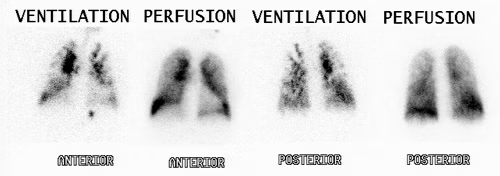

Lung Ventilation Perfusion (V/Q) Scan indications Nuc Med

Indication: Pulmonary Embolism

Lung Ventilation Perfusion scan Nuc Med vs CTPA

Lung (V/Q) Advantages:

Contrast allergy

Less ionising for pregnant patients

Can image those with renal impairments

Pharmaceuticals used in Lung (V/Q) scans

Ventilation= 99mTc Technegas

Perfusion= 99mTc MAA

PE Appearance in Lung (V/Q) scan

Normal ventilation, perfusion defect (mismatch)

Poor image quality causes for Lung V/Q scan

COPD= poor ventilation distribution